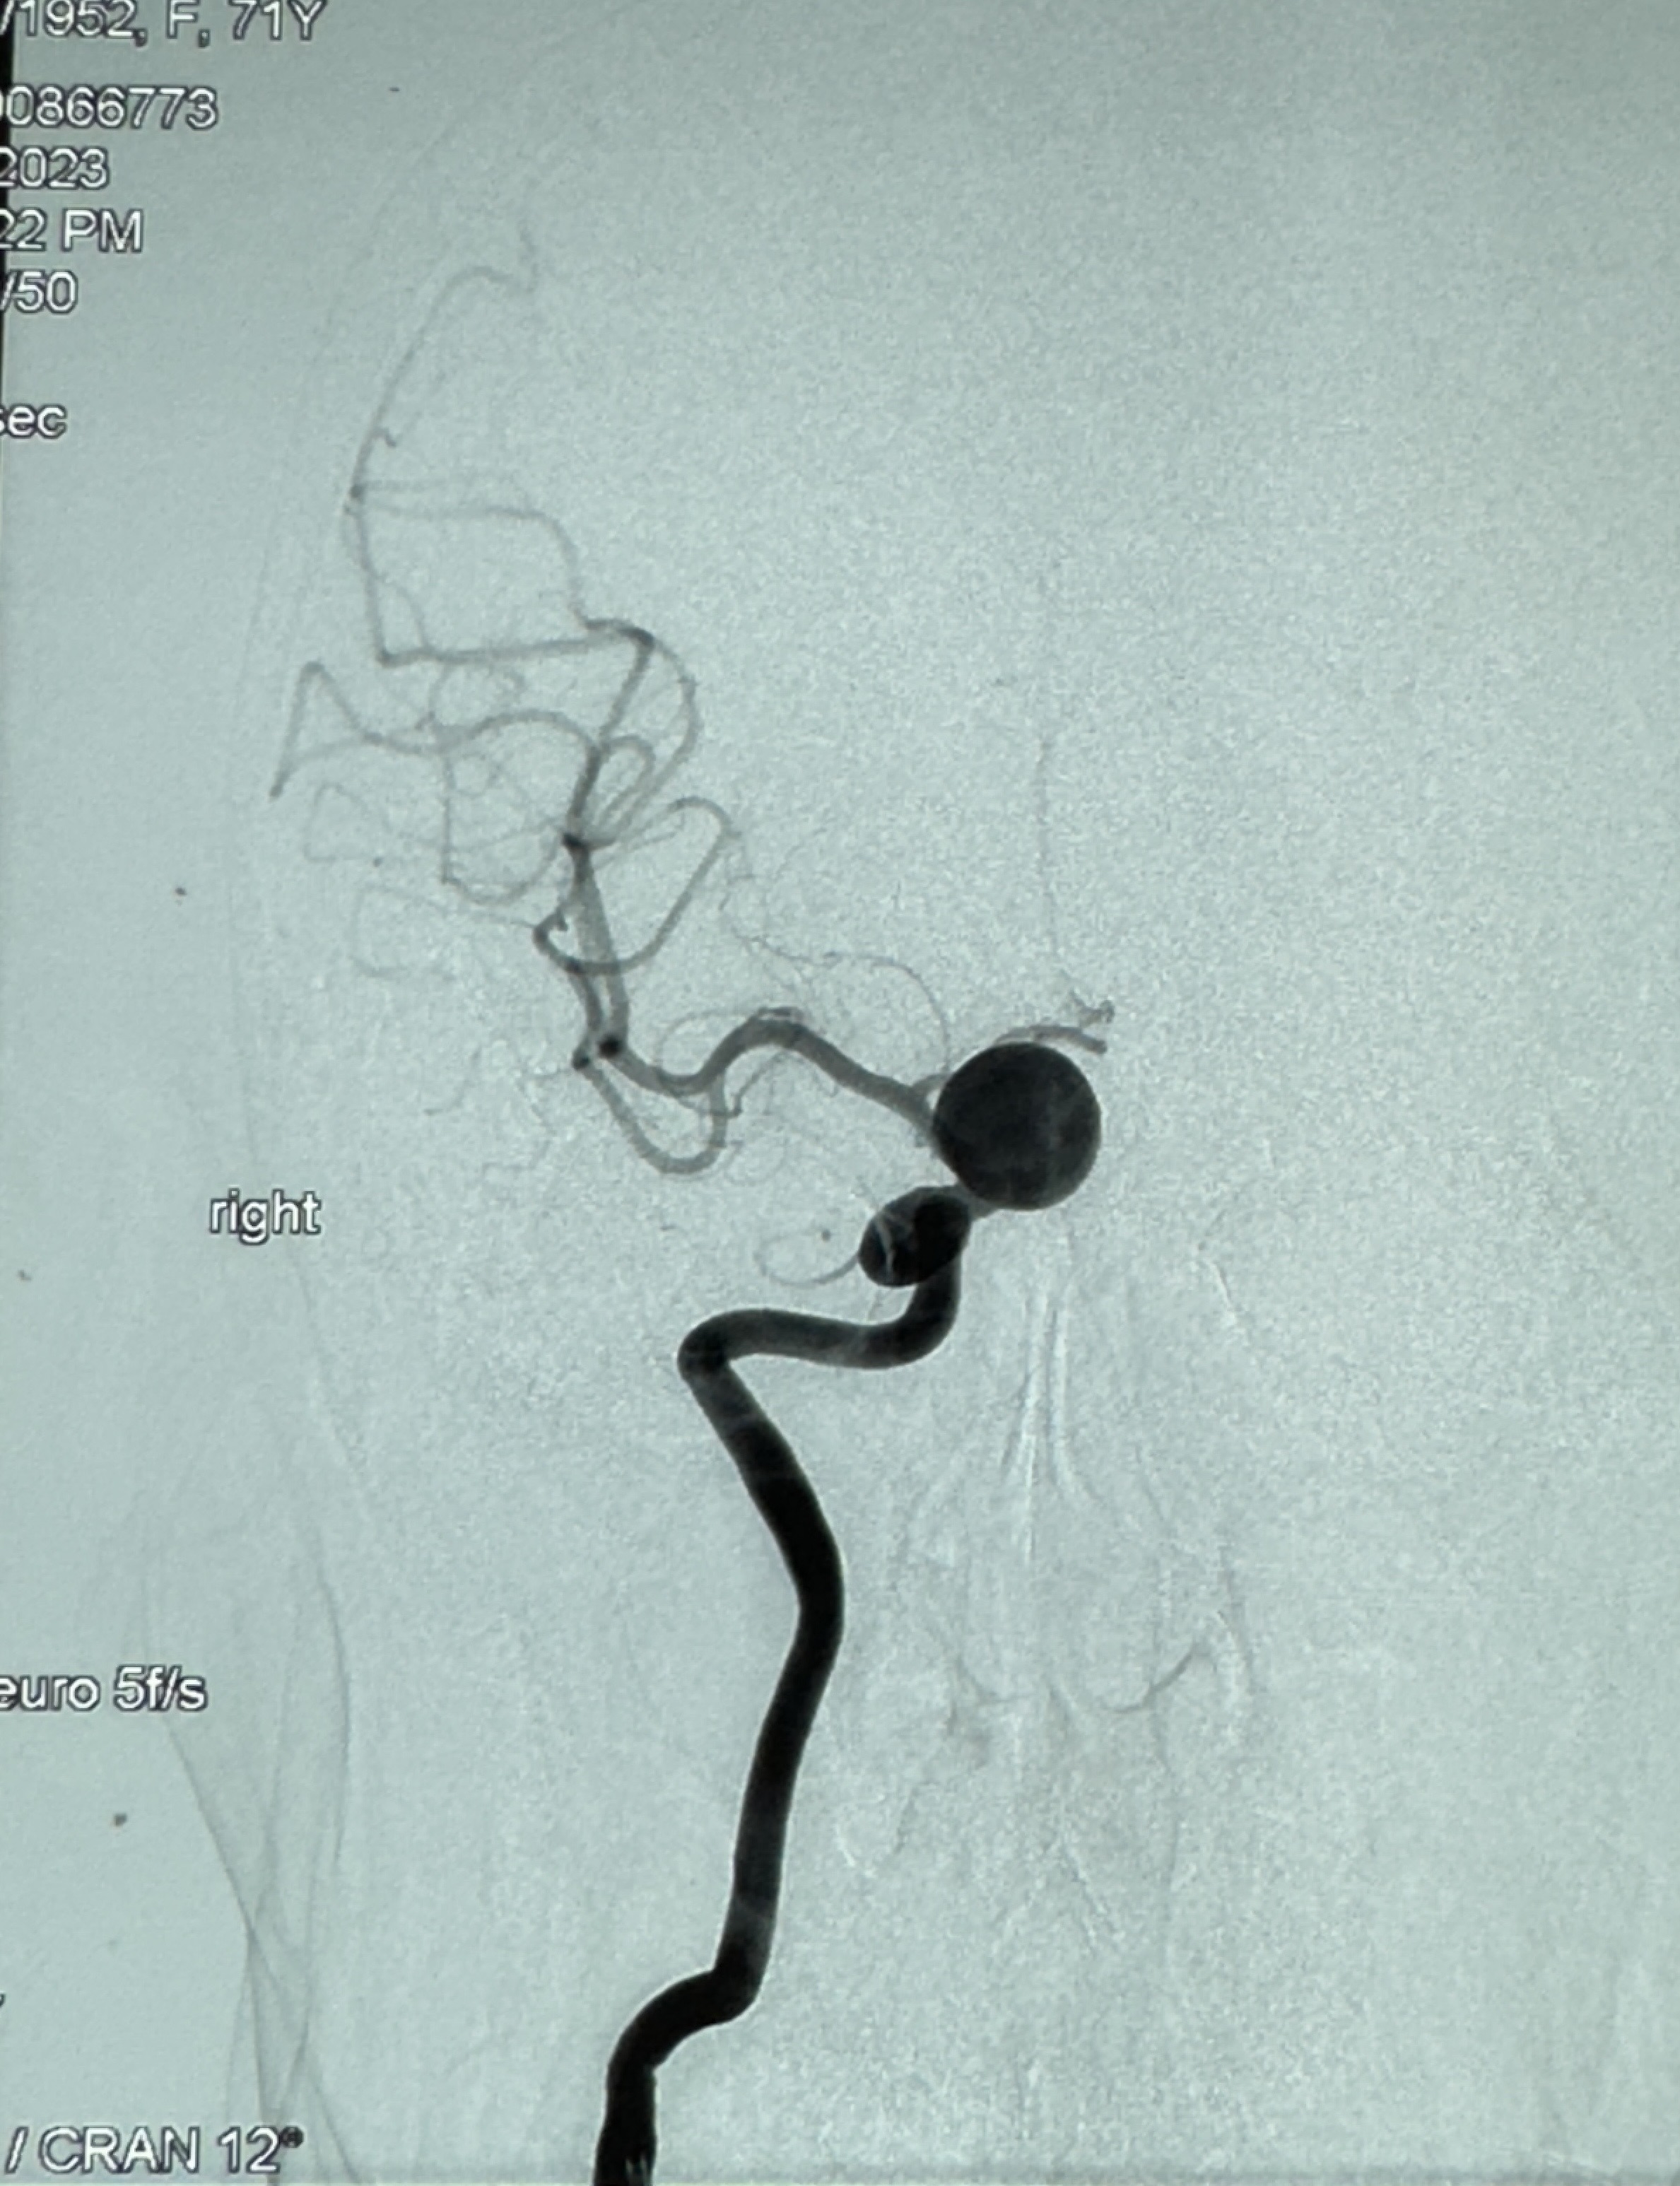

2023-12-08外院DSA:右侧颈眼动脉瘤,约13*12mm大小,压颈试验显示左右向及后向前代偿可

测量动脉瘤的大小:16*13.8*7.6mm大小,较原先变大,考虑双抗后瘤内血栓溶解可能

看动脉瘤内造影剂滞留,未见明确射流,遂撤出预留的栓塞微导管,快速结束手术,经导引导管灌注替罗非班250ug。

支架贴壁佳,但可见射流,咋办?